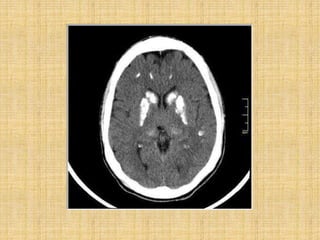

Fahr’s syndrome

• Idiopathic basal ganglia calcification

• Genetically dominant, inherited neurological

disorder most commonly affects lentiform

nucleus and Gpi.

• Occurs in 3rd to 5th decade.

• Deteriorization of motor function and speech,

seizure, involuntary movement, dementia,

headache, visual impairment.

• Unsteady gait, slurring of speech, difficulty in

swallowing ,clumsiness, fatiguability.

Fahr’s syndrome • Idiopathicbasal ganglia calcification • Genetically dominant, inherited neurological disorder most commonly affects lentiform nucleus and Gpi. • Occurs in 3rd to 5th decade. • Deteriorization of motor function and speech, seizure, involuntary movement, dementia, headache, visual impairment. • Unsteady gait, slurring of speech, difficulty in swallowing ,clumsiness, fatiguability.